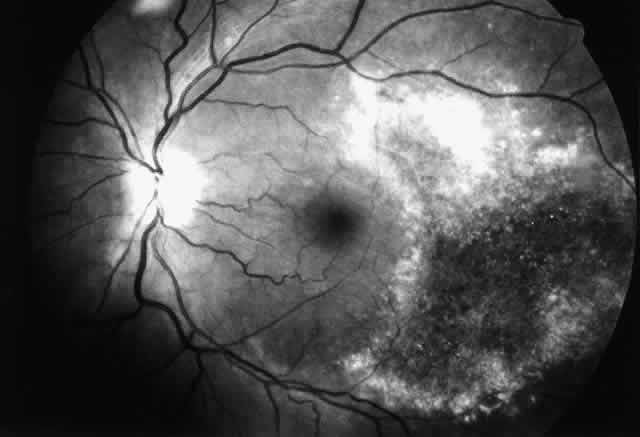

Cytomegalovirus (CMV) retinopathy is by far the most common of the severe ophthalmic infections in patients with AIDS. Varicella zoster virus retinopathy is being seen with increasing frequency; although it is probably the second most common retinal infection in North American HIV-infected patients, it is still far less common than CMV retinopathy. Toxoplasmic retinochoroiditis is the third retinal infection that is seen with some regularity, especially in certain areas of Europe and South America. The remaining retinal infections associated with AIDS are uncommon. They are seen with disseminated infections, in which the massive proliferation of organisms may overwhelm the patient's limited immune defenses. They are usually seen late in the course of the syndrome; thus, they may actually signal further waning of immune defenses. Patients with intraocular infections should be suspected of having tissue-invasive infections involving other internal organs. When they do occur, intraocular infections are frequently extensive and severe. Infections of the cornea and external eye are less common in HIV-infected individuals than intraocular infections. The natural defenses of normal eyelid function, tear film, and an intact corneal epithelium protect against many exogenous pathogens. It is therefore important that factors that might compromise those defenses, such as epithelial defects or trichiasis, be corrected as soon as possible. Also, HIV-infected patients who wear contact lenses should adhere strictly to lens care and disinfection techniques. Many HIV-infected individuals appear to have decreased aqueous tear production, which leads to feelings of dryness and irritation but does not seem to result in an increased incidence of ocular surface infections. At greater risk are patients who have permanent damage to the eyelids from zoster ophthalmicus, neurotrophic corneas from herpetic infections, or damage to the ocular surface from cicatricial conjunctivitis, similar to that of Stevens-Johnson syndrome, which is seen occasionally in patients with AIDS. HIV infection and its sequelae are being studied in a variety of animal models. Rhesus monkeys infected with simian immunodeficiency virus develop an AIDS-like illness. In this model the monkeys develop a variety of ophthalmic lesions, including CMV infections of the retina.10 This model may be useful for future studies of AIDS-related ophthalmic infections. CYTOMEGALOVIRUS Cytomegalovirus retinopathy is the most thoroughly studied of the ophthalmic manifestations of HIV infection. CMV retinopathy is an AIDS-defining index disease. Most studies have concentrated on treatment, but a great deal has been learned about the natural history of CMV retinopathy during the course of these studies. Cytomegalovirus is a ubiquitous DNA virus of the herpes group. Most of the adult population has been infected with CMV, but in most cases it does not cause any clinically apparent disease. The virus remains in the body, however, as a latent infection. In patients with AIDS, CMV can cause life-threatening infections involving many tissues, including the brain, lungs, and gastrointestinal tract. The reported prevalence of CMV retinopathy varies from 4% of ambulatory patients (primarily intravenous drug abusers)11 to 34% of eyes in an autopsy series of male homosexuals.9 This discrepancy may reflect the fact that CMV retinopathy occurs late in the course of AIDS. Most investigators believe that the true prevalence of CMV retinopathy among patients with AIDS is approximately 15% to 25%. It has been suggested that CMV retinopathy is more common in homosexuals, because of different levels of exposure to CMV between risk groups.11,12 Cytomegalovirus retinopathy is clearly a disorder of immunosuppressed persons. Prior to its association with AIDS, the infection in adults was seen almost exclusively in patients with defects in cellular immunity related to disease or immunosuppressive drugs.13,14 A single report of CMV retinopathy in a healthy adult was not confirmed by culture or tissue examination.15 There is no obvious correlation between the development of CMV retinopathy and levels of CMV antibodies. CMV retinopathy has been reported in the absence of detectable antibodies.16 Histologic studies of AIDS-related CMV retinopathy demonstrate the tissue necrosis and cytomegalic cells characteristic of all CMV infections (Fig. 1).9,17 Electron-microscopic and immunochemical studies have identified CMV viral particles and antigen in a patchy distribution throughout all layers of the retina and occasionally in contiguous retinal pigment epithelial cells.9 Viral antigens are only rarely identified in the choroid.9,18 Viral antigen in the choroid has been found in association with vessels and is not always adjacent to areas of retinopathy, suggesting that the virus reaches the choroid through independent hematogenous spread rather than by extension of infection from the retina. Among cases of AIDS examined at autopsy, 22% to 50% of those with CMV retinopathy have neutrophilic infiltrates in retinal tissue.9,19 This finding is atypical when compared with CMV retinopathy in non-AIDS patients, in which only a sparse lymphocytic infiltrate is observed. The difference has been attributed to intact granulocyte function and chemotaxis in patients with AIDS, in contrast to infants, organ transplant recipients, and patients with malignancies who can have more severe quantitative or qualitative granulocyte dysfunction.9 It has been noted that patients on immunosuppressive drugs can develop marked inflammatory reactions to CMV retinopathy when such drugs are withdrawn.14 Acute inflammatory cells may extend into the adjacent choroid despite the absence of identifiable viral antigens.9 The vitreous usually remains remarkably free of inflammatory material, despite the presence of virus in the vitreous cavity.20 A variety of stimuli (CMV antigen, immune complex deposition, and tissue necrosis) may be responsible for the production of chemotactic factors leading to neutrophilic infiltration. Immunochemical studies have revealed deposition of IgG, IgA, and, to a lesser extent, IgM and C3c in retinal tissue and within retinal arteriolar walls.9 Many IgA-bearing plasma cells were present in one case.17 Perivascular infiltration of neutrophils occurs, consistent with immune complex-mediated vasculitis,9,17 but there is poor correlation between the distribution of tissue-bound immunoglobulins, acute inflammatory cells, and CMV antigens.9 Thus, it is also possible that concurrent retinal infection with other as-yet-unidentified pathogens is responsible for the acute inflammatory reaction seen in these eyes. Inflammatory cell products do not appear to play a significant role in the extensive tissue destruction common to all cases of CMV retinopathy. The histopathologic characteristics of AIDS-related CMV retinopathy in one autopsy study are listed in Table 3.9 CMV retinopathy frequently begins adjacent to retinal vessels in the posterior pole (Fig. 2). It is believed that virus reaches the eye via the bloodstream. Untreated CMV retinopathy in patients with AIDS is a relentlessly progressive disease. Usually, infection begins with an isolated focus of disease; rarely are there more than two or three discrete areas of infection within the eye. These lesions invariably enlarge to involve additional retinal tissue. New lesions develop less frequently. The enlargement of lesions does not progress at the same rate from all lesion borders.21 The rate of progression is faster in an anterior direction toward the ora serrata than in a posterior direction toward the fovea. CMV retinopathy has been considered a “foveal-sparing” disease. In a series of organ transplant patients with CMV retinopathy reported by Egbert and associates prior to the AIDS epidemic, only 3 of 21 eyes had macular involvement.14 The higher incidence of macular involvement in early autopsy series of patients with AIDS may reflect the fact that progression of CMV retinopathy into the macular region could not be stopped prior to the introduction of ganciclovir and foscarnet therapy. Even though the fovea can eventually be destroyed, it is usually the last area to become infected; in some cases the disease appears to move circumferentially around the fovea (Fig. 3). Eventually the entire retina will be destroyed, usually within a 6-month period.19 Progression of the retinopathy halts abruptly at the ora serrata.9 Following total retinal necrosis, it is replaced by a thin gliotic membrane.19 No virus can be identified in ocular tissue at this late stage.